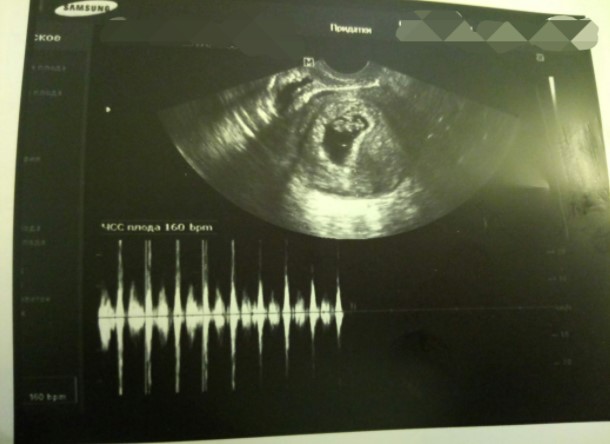

Только тот, кто сам прошёл через подобное может понять то чувство, когда узнаешь, что эмбрион прижился, когда видишь свой анализ ХГЧ! На радостях сама отменила себе все медикаменты и чуть горько не поплатилась за это - на первом же УЗИ после ХГЧ сердцебиение плода было, а доктор поставила угрозу выкидыша из-за гипертонуса матки! Лекарства вернули, тонус пропал, угроза выкидыша снялась.

Фото - узи плода 8 недель